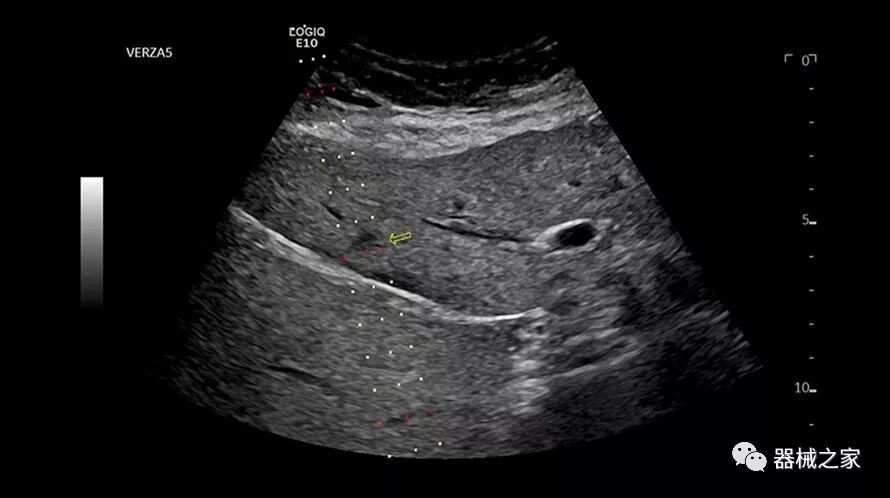

Baptist Health South Florida成为去年秋天西门子医疗保健公司Acuson Sequoia的首个商业安装网站。该系统将有助于增强胃肠病学,初级保健和减肥专业的成像能力。Sequoia可实现高分辨率成像,自动适应患者的体型和个人身体特征,有助于更加自信的诊断。它适应患者的组织密度,刚度和超声波束吸收的生物声学变化。这使得系统可以穿透高达40厘米而不会因衰减回波信号而导致图像质量下降。

Acuson Sequoia